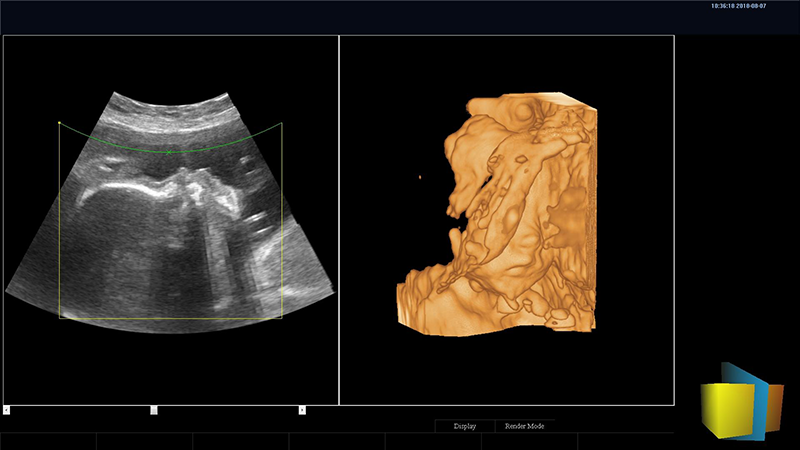

DW-T8四維彩超機

四維圖像